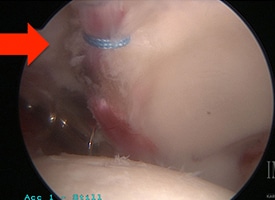

POST OP

This arthroscopic photo demonstrates a labral repair.